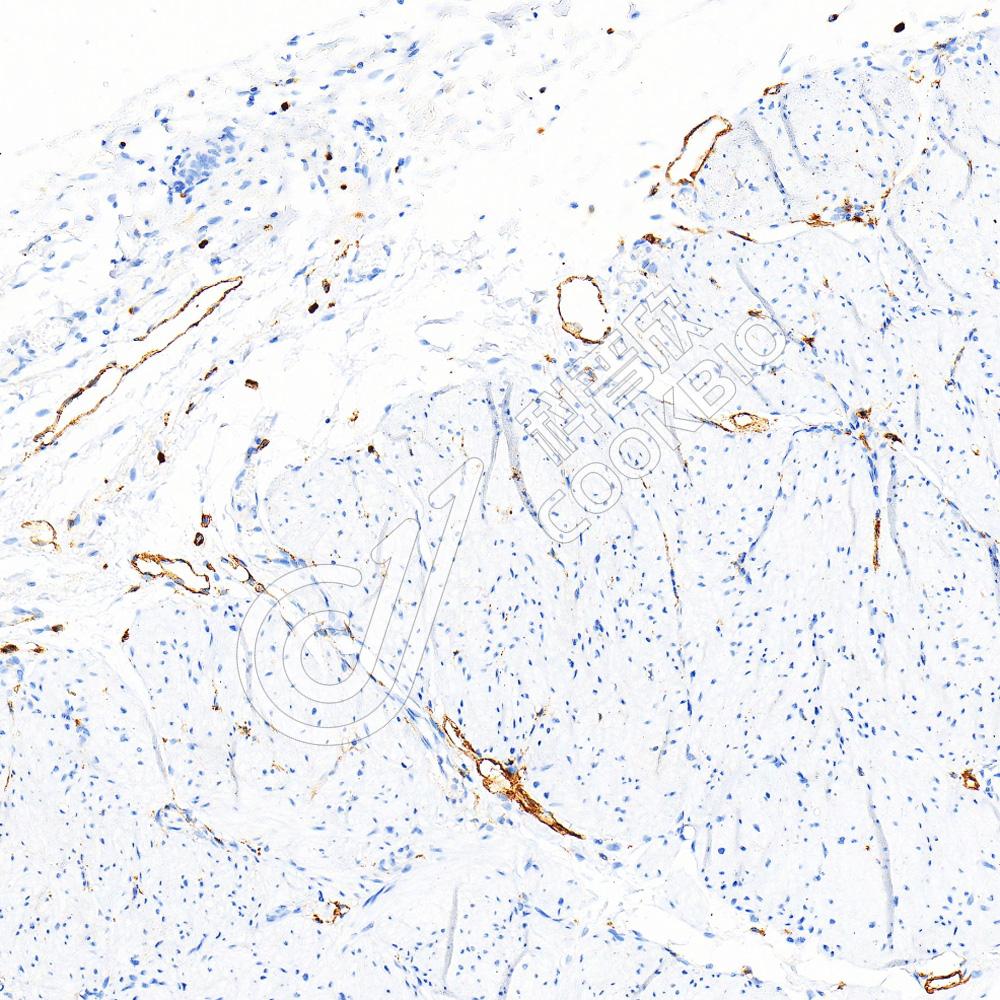

IHC检测eNOS蛋白(货号 K236258).

样品: 大鼠肺, 4%多聚甲醛 (货号KSG1101) 固定12-24小时.

抗原修复: 柠檬酸抗原修复液(干粉, pH 6.0) (KSG1201), 高压锅均匀喷气计时2分钟.

—抗: 1: 1300稀释, 4℃ 孵育过夜.

二抗: S-vision免疫组化多聚二抗(山羊抗小鼠), 即用型(货号KB3903), 室温孵育20分钟.